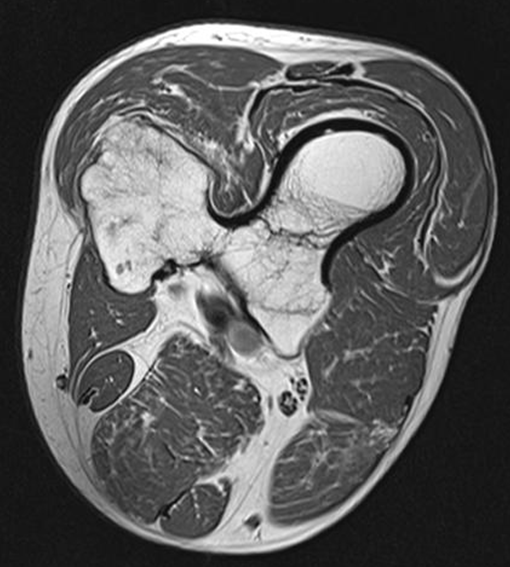

Osgood Schlatter

Incomplete separation or avulsion of the tibial tuberosity.

Cause: Repeated stress to tibial tuberosity growth plate

•stress will lead to the tendon pulling away

Complications: are uncommon, chronic pain or localized swelling,

bump in the area

Radiographic Appearance: prominent soft tissue swelling and an avulsed ossific fragment

Technical: No manual exposure factor change

Prognosis: good, resolves normally on its own once the bones

stop growing

Osteochondroma

(Exostosis)

Benign projection of bone with a cartilaginous cap

Cause: idiopathic, hereditary

Complications: may turn malignant, pain, fracture of stalk

Radiographic Appearance: long axis of bone growth runs parallel to the parent bone and points away from nearest joint

Prognosis: Good, surgery only needed when there are mechanical

impingements